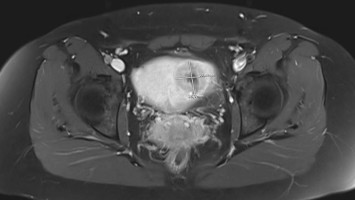

Akuter Harnverhalt in der Frühschwangerschaft

Eine 41-jährige III-Gravida I‑Para – Zustand nach Sectio – stellt sich mit Unterbauchschmerzen und tropfenweiser Harninkontinenz in der 11. Schwangerschaftswoche vor. Es besteht keine vaginale Blutung, gastroenterologische Ursachen sind ausgeschlossen. Was war der Grund für die Beschwerden?